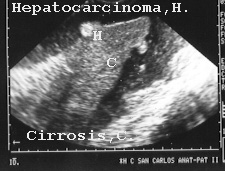

La patología en el hígado fue fácil de demostrar. Como ejemplos presentamos las figuras 15, 16 y 17 de cirrosis, cirrosis con hepatocarcinoma y de metástasis tumoral.

16HEPATO.JPG (20569 bytes)

Fig 16